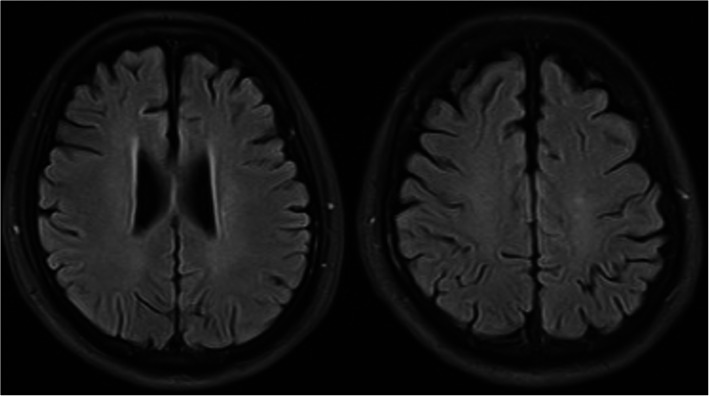

Four days after admission, the mechanical ventilator was removed, and the blood oxygen saturation of this patient was normal. After this treatment combination was administered for 33 days, the patient’s sensorium improved with eye opening in response to painful stimuli. Forty-six days later, he could open his eyes and had some tracking eye movement. He could open his eyes to verbal stimuli and perform some simple body movements, but he did not speak coherently. Fifty-five days later, his consciousness gradually became normal, and he underwent internal fixation surgery for a right lower limb fracture. Figure 3 shows his head MRI results 11 months after the car accident, and the lesions were almost completely absorbed. The Barthel index was 95 at the last visit 10 months later.

Fig. 3.

Head MRI of this patient re-examined 11 months after the car accident showed that the “star field” pattern lesions were almost completely absorbed